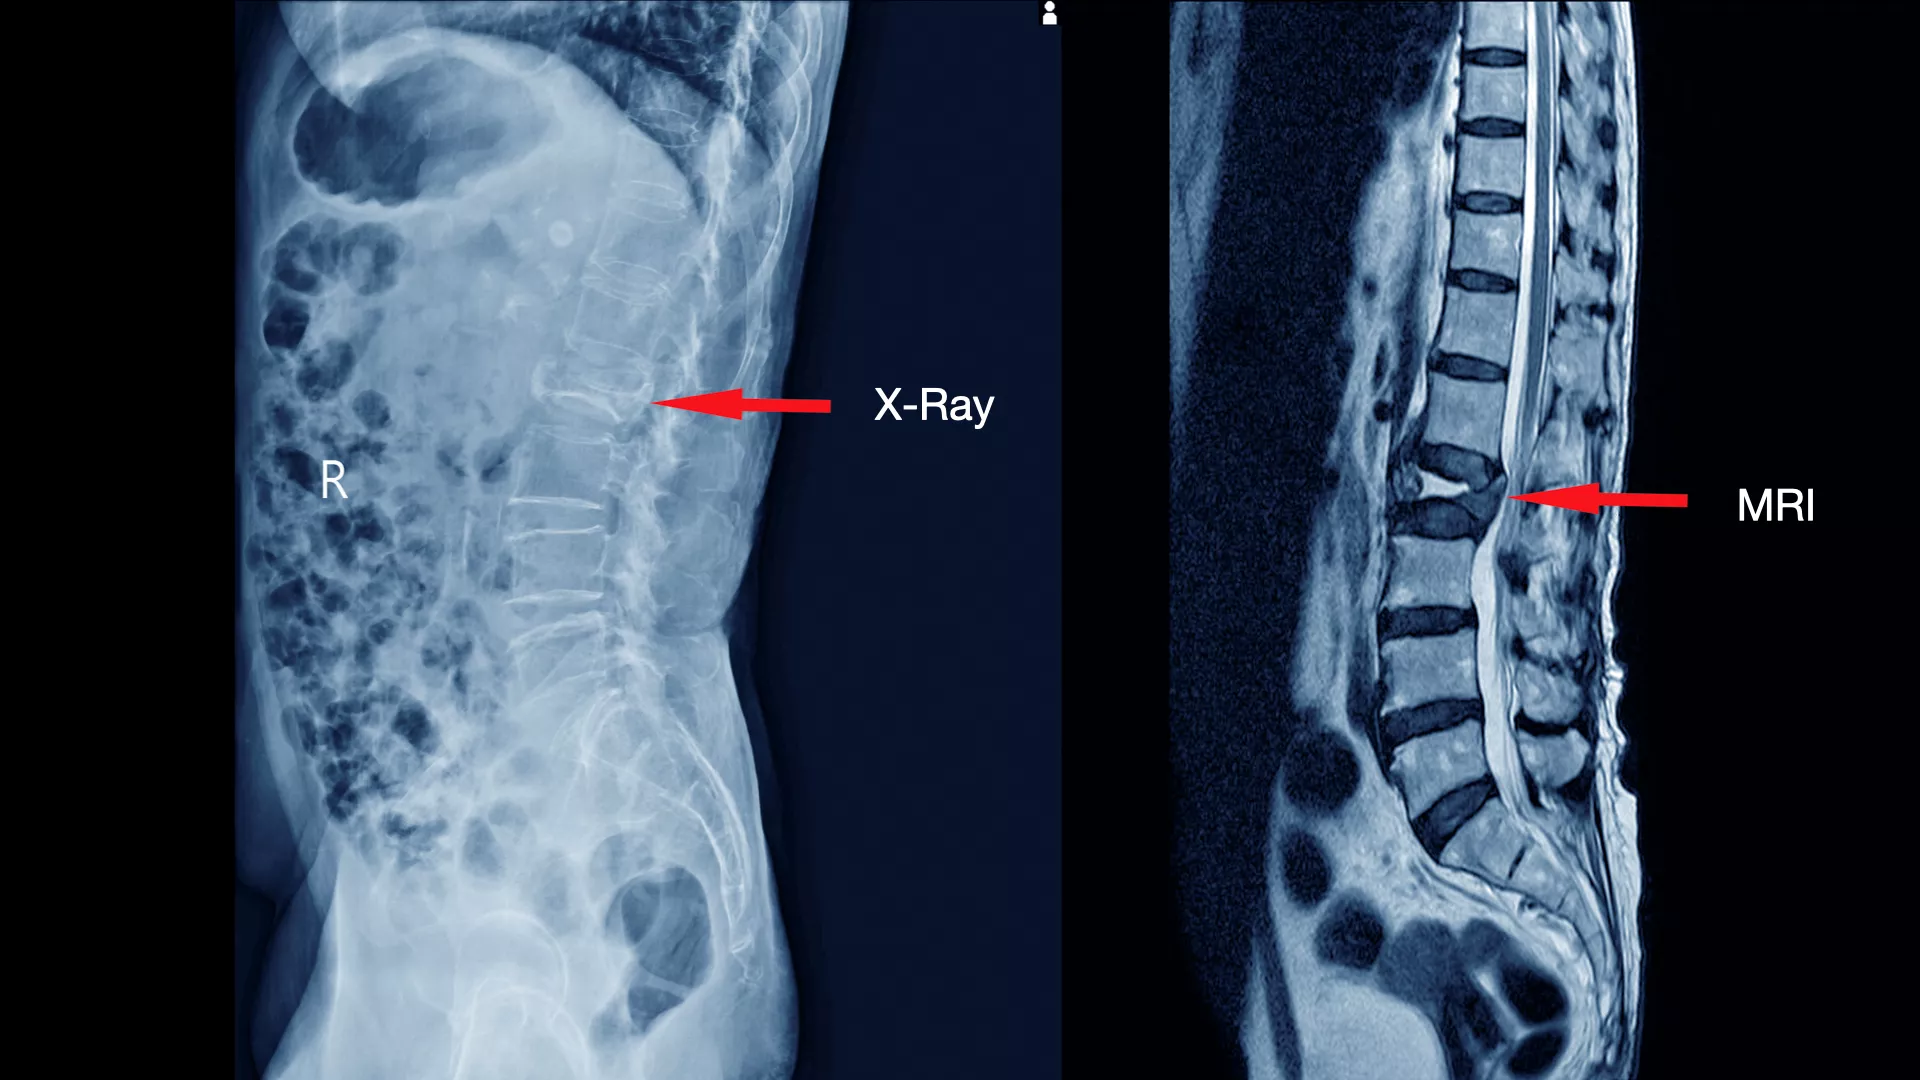

ดังนั้นการตรวจด้วย X-ray ทั้ง 4 ท่านี้จะช่วยให้แพทย์สามารถประเมินโครงสร้างของกระดูกสันหลังได้อย่างละเอียด และเป็นข้อมูลสำคัญในการพิจารณาแนวทางการรักษาที่เหมาะสมสำหรับผู้ป่วยแต่ละราย นอกจากนี้ การตรวจด้วย MRI (Magnetic Resonance Imaging) หรือ การสร้างภาพอวัยวะภายในร่างกายด้วยคลื่นแม่เหล็กไฟฟ้าและคลื่นวิทยุ โดยไม่ต้องใช้รังสีเอกซเรย์ที่เป็นอันตราย ก็มีความสำคัญอย่างยิ่งในการวินิจฉัยโรคกระดูกสันหลัง

การตรวจด้วย X-ray ทั้ง 4 ท่าจะช่วยให้แพทย์ประเมินภาพรวมของโครงสร้างกระดูกได้อย่างละเอียด แต่ X-ray ไม่สามารถแสดงภาพของเนื้อเยื่ออ่อน (Soft Tissue) เช่น หมอนรองกระดูก เส้นประสาท และไขสันหลัง ได้อย่างชัดเจน

ดังนั้น การตรวจด้วย MRI จึงเข้ามาเติมเต็มในจุดนี้ โดยจะะให้ภาพที่มีความละเอียดสูงและสามารถเห็นรายละเอียดของเนื้อเยื่ออ่อนและลักษณะของรอยโรคได้อย่างชัดเจน ทำให้แพทย์สามารถ

- ระบุตำแหน่งและขนาดของรอยโรคได้อย่างแม่นยำ เช่น หมอนรองกระดูกปลิ้น หรือ หมอนรองกระดูกทับเส้นประสาท

- ประเมินความเสียหายของเส้นประสาท เห็นถึงระดับการกดทับของเส้นประสาทและไขสันหลัง

- วางแผนการรักษาได้อย่างถูกต้อง ช่วยให้แพทย์ตัดสินใจได้ว่าควรใช้วิธีการรักษาแบบไม่ผ่าตัด เช่น กายภาพบำบัด ทานยา หรือจำเป็นต้องผ่าตัด

การตรวจทั้ง X-ray และ MRI ร่วมกันจึงเป็นการผสมผสานที่สมบูรณ์แบบ เพื่อให้แพทย์ได้ข้อมูลที่ครอบคลุม ครบถ้วนและแม่นยำที่สุด สำหรับการวินิจฉัยและวางแผนการรักษาที่เหมาะสมสำหรับผู้ป่วยแต่ละราย